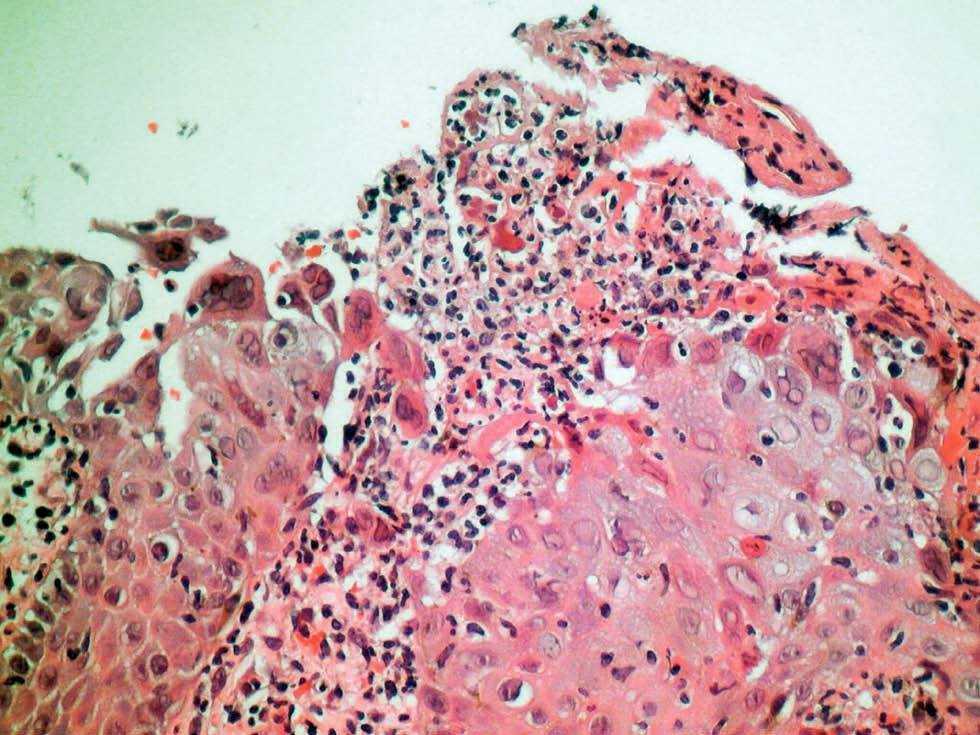

El estudio histopatológico del borde de una úlcera perianal mostró células gigantes en la epidermis y balonización y necrosis de queratinocitos (fig. 3). Los cultivos para bacterias y hongos fueron negativos, la fluorescencia directa para VHS positiva y la serología específica para el VHS-2 también positiva. Se observó una rápida mejoría con resolución completa de las úlceras tras dos semanas de tratamiento con aciclovir oral (200 mg 5 veces al día). Dos meses después tuvo un nuevo brote de lesiones localizadas en la mano izquierda.

Fig. 3.--Células gigantes multinucleadas en la epidermis y balonización de los queratinocitos (hematoxilina-eosina, ×200).